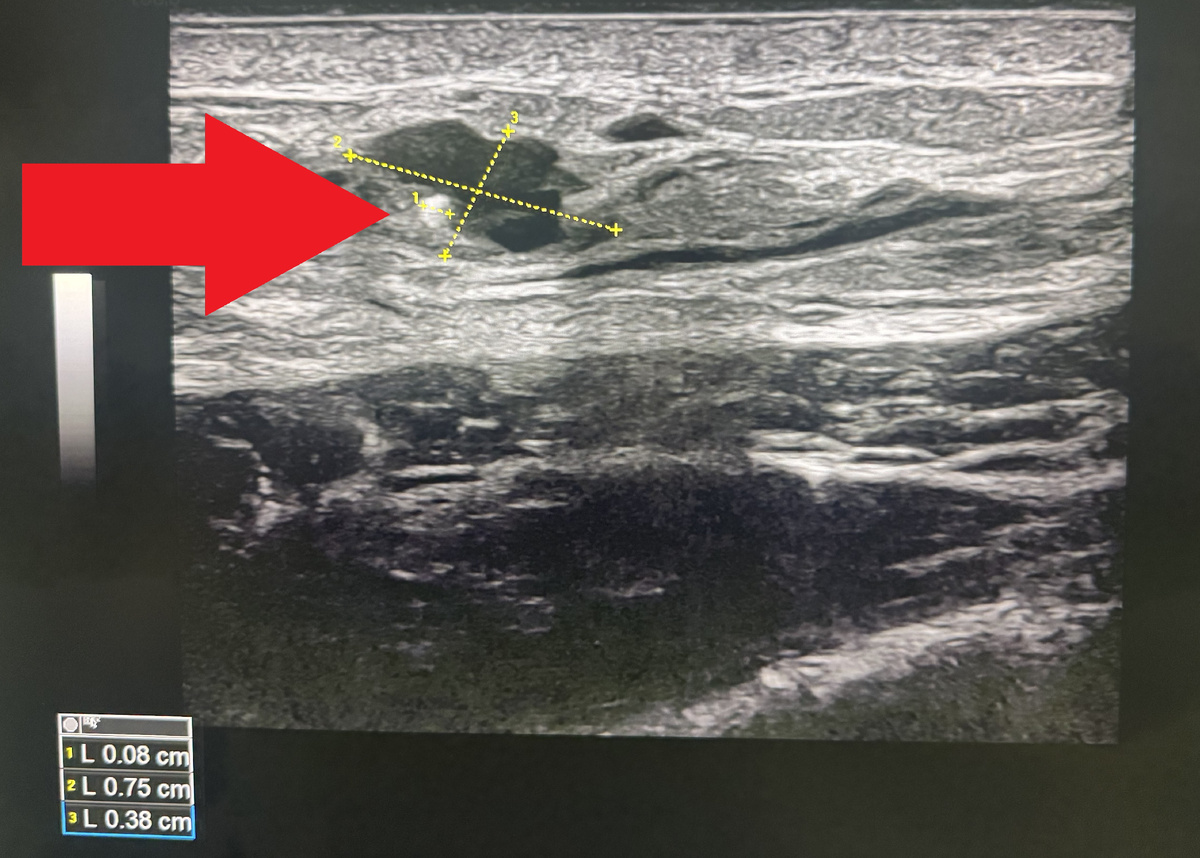

На фото ниже представлен снимок УЗИ молочных желез, на котором определяется киста с перегородками. В стенке кисты четко виден округлое белое включение - микрокальцинат.

Размеры кисты 7,5 х 4 мм, а диаметр самого микрокальцината при этом всего 0,8 мм.

Подобное новообразование не является опасным, не требует биопсии или каких-либо дополнительных уточняющих диагностических процедур. Тактика - ежегодное динамическое УЗИ-наблюдение.